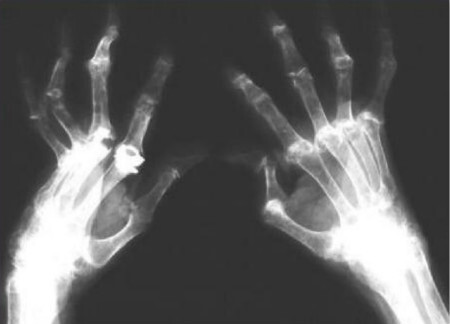

类风湿关节炎就是一种病因未明的慢性、以炎性滑膜炎为主的系统性疾病。类风湿关节炎疾病的特征主要表现为手、足小关节的多关节、对称性、侵袭性关节炎症,并且常伴有关节外器官受累及血清类风湿因子阳性,可以导致患者的关节畸形以及功能丧失。于是,很多患者都想知道一个对于他们来说很重要的问题,那就是:类风湿关节炎会导致人死亡吗?

当然,类风湿关节炎这种疾病最大的特点是使人出现关节畸形。而且,根据临床观察,在所有的疾病中,类风湿关节炎的致畸率、致残率是最高的。因此,类风湿性关节炎治疗早期确诊并治疗是非常关键的。类风湿病的关节的肿胀疼痛,往往是对称性的,持续时间比较长,这就需要进行详细的检察后进而明确诊断,使类风湿关节炎得以早期发现和治疗,争取在类风湿关节炎进展到关节畸形前就得到扼制。